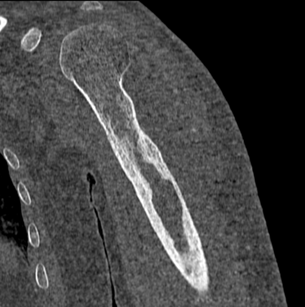

Bone marrow aspiration from left humerus - Narayana Imaging & Diagnostics